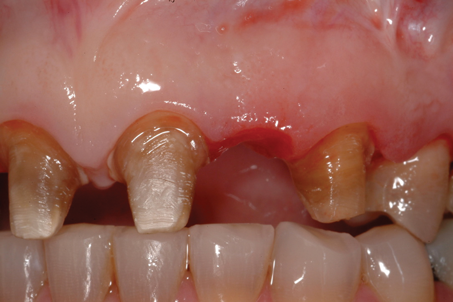

(12.) Bone sounding was performed to confirm that there was at least 2 mm from the base of the pontic sites to the alveolar bone.

Figure 12

The distance between the bottom of the ovate pontic site and the alveolar bone is determined using a periodontal probe to sound for the bone. If the measured distance is 2 mm or greater (Figure 4), then there is adequate tissue thickness to meet the prosthetic biologic width requirements, and the provisional restoration can be cemented with provisional cement. However, if the tissue thickness is less than 2 mm, then there is not adequate tissue present to meet the prosthetic biologic width requirements (Figure 5), and the pontic site must be deepened using a teardrop-shaped diamond bur (Figure 6). The remaining soft tissue and enough alveolar bone are removed to result in the required 2-mm distance from the most subgingival aspect of the pontic to the alveolar bone. It is essential that the intaglio surface of the pontic be correctly contoured before the reshaping of the pontic site. The provisional bridge can then be cemented with a provisional cement and the provisional pontic will direct the regrowth of the soft tissue.

A patient presented with two defective 3-unit fixed partial dentures spanning teeth Nos. 6 through 8 and teeth Nos. 9 through 11 (Figure 7). The defective fixed partial dentures were removed (Figure 8), an impression was made, and traditional provisional fixed partial dentures without ovate pontics were placed. After the impression was sent to the laboratory, the lab technician prepared ovate pontic sites on the stone cast (Figure 9) and fabricated the new definitive bridges. On the day of insertion, the provisional fixed partial dentures were removed (Figure 10), ovate pontic sites were prepared using a teardrop-shaped diamond bur (Figure 11), and the sites were sounded to confirm that there was at least 2 mm from the base of the pontic site to the alveolar bone (Figure 12). The fixed partial dentures were cemented, and the postoperative healing was uneventful (Figure 13).